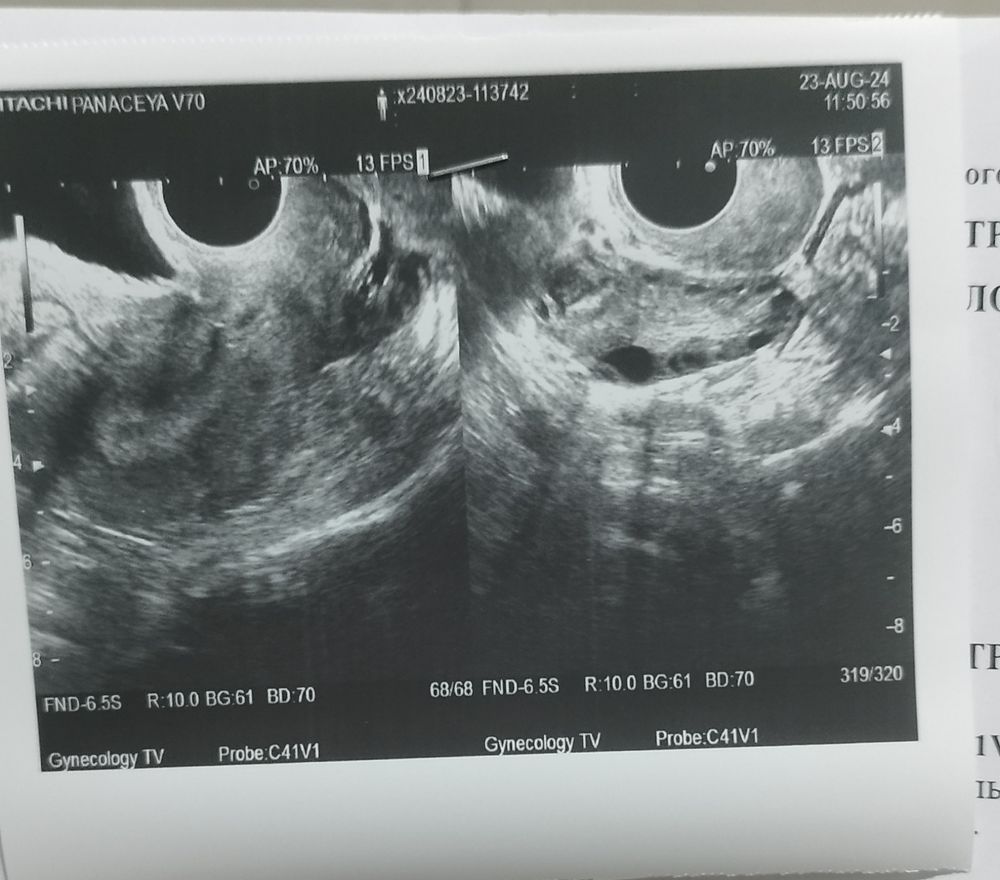

Добрый день, помогите разобраться в УЗИ, может ли быть беременность, есть признаки Б, но по ним не реально ориентироваться, признаки у меня эти же присутствуют перед М.... Что за пятна чёрные на 2 фото УЗИ? Болит живот периодами,то проявится боль,то пропадет, сегодня под вечер поднялась температура 37.3, болит горло и прям недомогание.... По УЗИ сказали что овуляции была, и норма ли что выявлена жидкость в позадиматочном пространстве? Врач УЗИ толком ни чего не сказала к Г запись только через 2 недели, а по фото УЗИ абсолютно не чего не понятно...

Вам в заключении написали ретенционное образование правого яичника , так характеризуют кисты. УЗИ более информативно с 5-7 день цикла.

Жидкость в позадиматочном обычно от овуляции бывает.